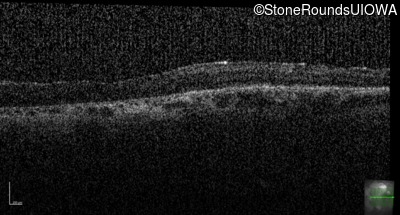

Optical Coherence Tomography - Right - 20/100 +1

Exemplar / OCT Stack